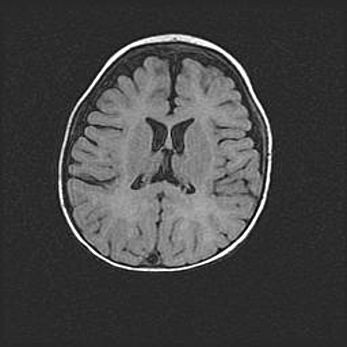

Церебральная ишемия II.

Возраст: 7 дней

Вес: 3350 г

Пол: женский

Окружность головы: 35 см

Срок гестации: 39 недель

Ишемия головного мозга – это состояние, которое развивается в ответ на кислородное голодание вследствие недостаточного мозгового кровообращения. У новорожденных она является следствием дефицита кислорода, что ведет к метаболическим расстройствам различной степени тяжести в тканях головного мозга, в том числе к развитию коагуляционных некрозов и гибели нейронов.